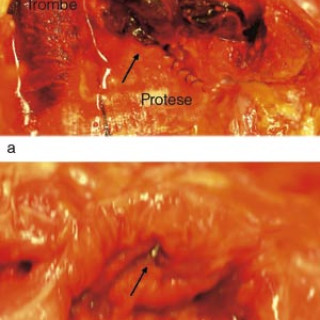

En 52 år gammel etnisk norsk mann ble innlagt i psykiatrisk akuttavdeling etter noen få uker med kraftig økende aktivitetsnivå. Han hadde vist markant endret atferd – blant annet hadde han satt seg fore å sykle åtte mil i kuldegrader og slaps. Ved innleggelsen var han irritabel og snakket fort og nærmest usammenhengende. Somatisk status presens ved innkomst samt orienterende nevrologisk status var normale. Vanlige blodprøver ved innleggelse, inklusive Hb, SR, hvite blodceller, kreatinin, natrium, kalium, ALAT, ASAT, ferritin, folat, kobalamin, FT4, TSH, var alle innenfor referanseområdet...